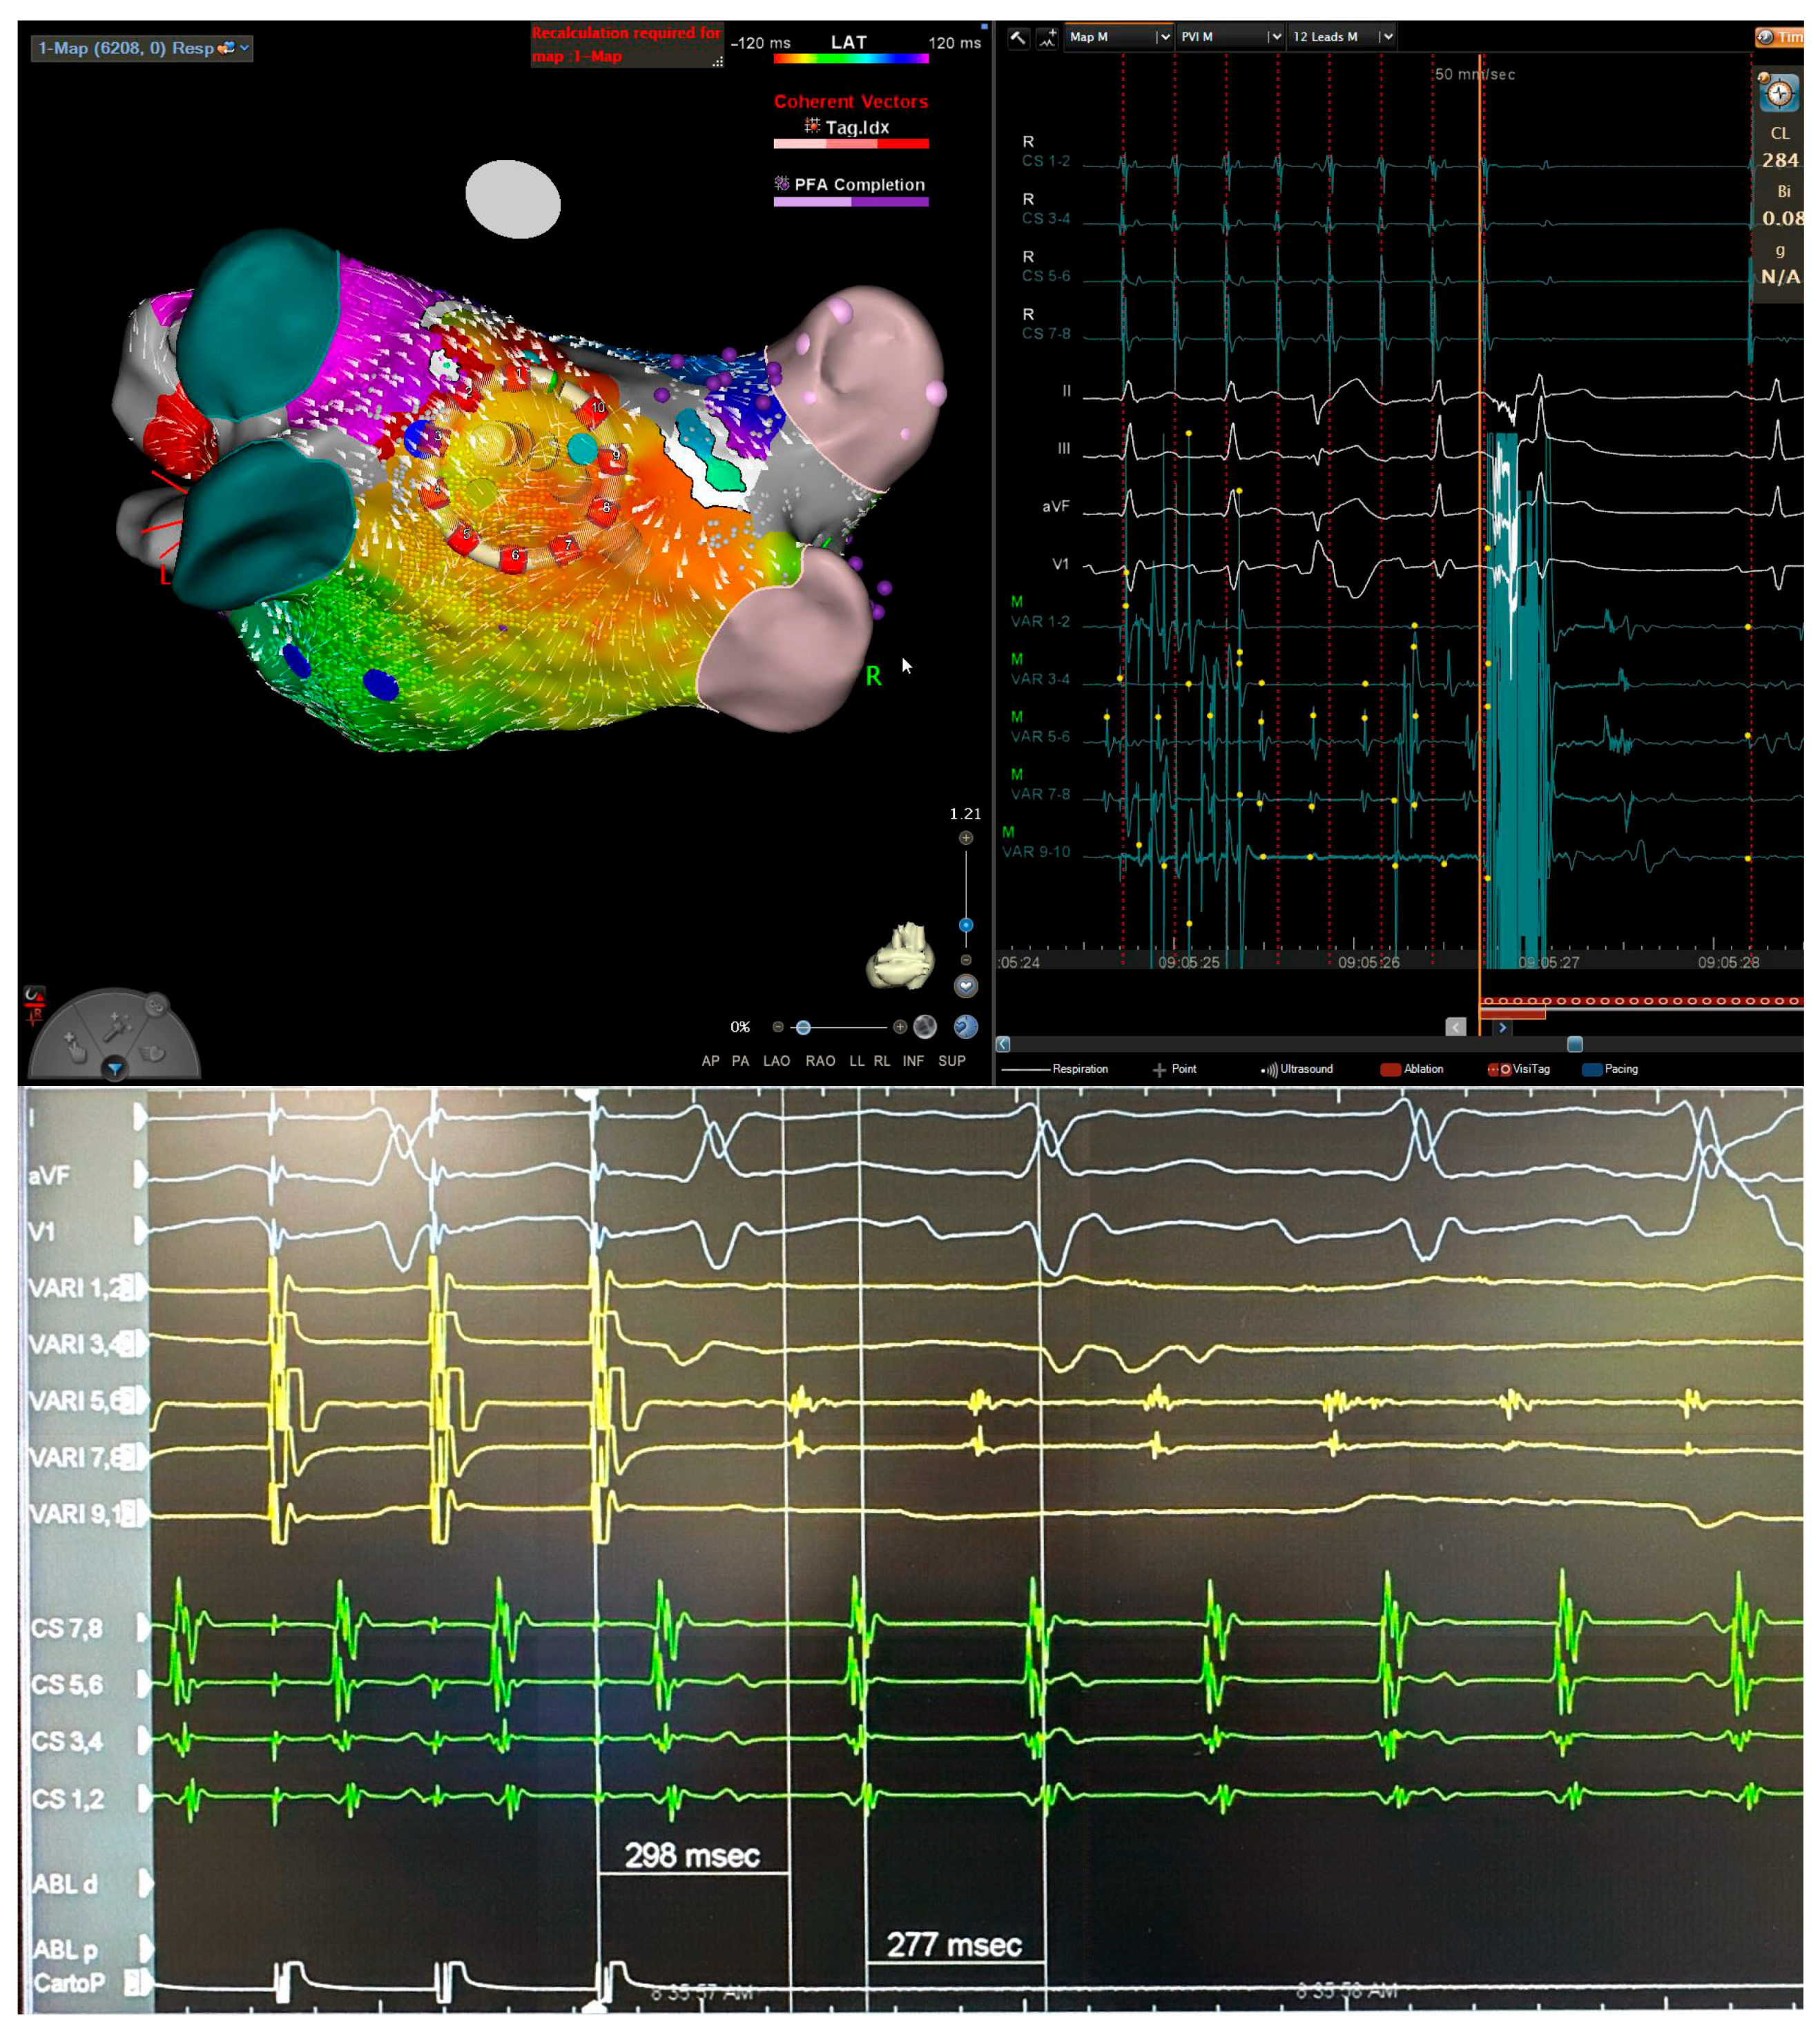

VARIPULSE: A step‐by‐step guide to pulmonary vein isolation | Cody ...

Near-zero fluoroscopy workflow for pulmonary vein isolation in atrial ...

Mapping and ablation of left atrial macro-reentrant tachycardia with a ...

VARIPULSE: A step‐by‐step guide to pulmonary vein isolation - Nair ...

Pulsed field ablation for complex variant pulmonary vein and posterior ...